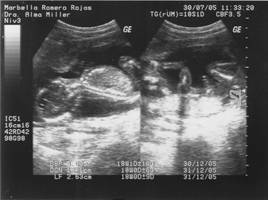

La imagen de ultrasonido aparece inmediatamente en una pantalla similar a una pantalla de computadora o televisión. El radiólogo o ecografista mira esta pantalla durante el examen y captura imágenes representativas para guardarlas. A menudo el paciente también puede ver las imágenes.

El transductor funciona como amplificador (para crear el sonido) y como micrófono (para grabarlo). Cuando el transductor se coloca contra la piel le dirige al cuerpo una corriente de ondas de sonido inaudible de la frecuencia. El sensible micrófono del transductor registra la fuerza y las características de las ondas que rebotan de los líquidos y tejidos del cuerpo. En el ultrasonido Doppler el micrófono capta y registra pequeños cambios en el tono y la dirección de la onda. La computadora inmediatamente mide y visualiza estas ondas y crea una imagen en tiempo real en el monitor. Las imágenes “en vivo” del examen se pueden grabar en una videocinta o en disco. Además, por lo general se toman fotografías estáticas de una serie de imágenes en movimiento.